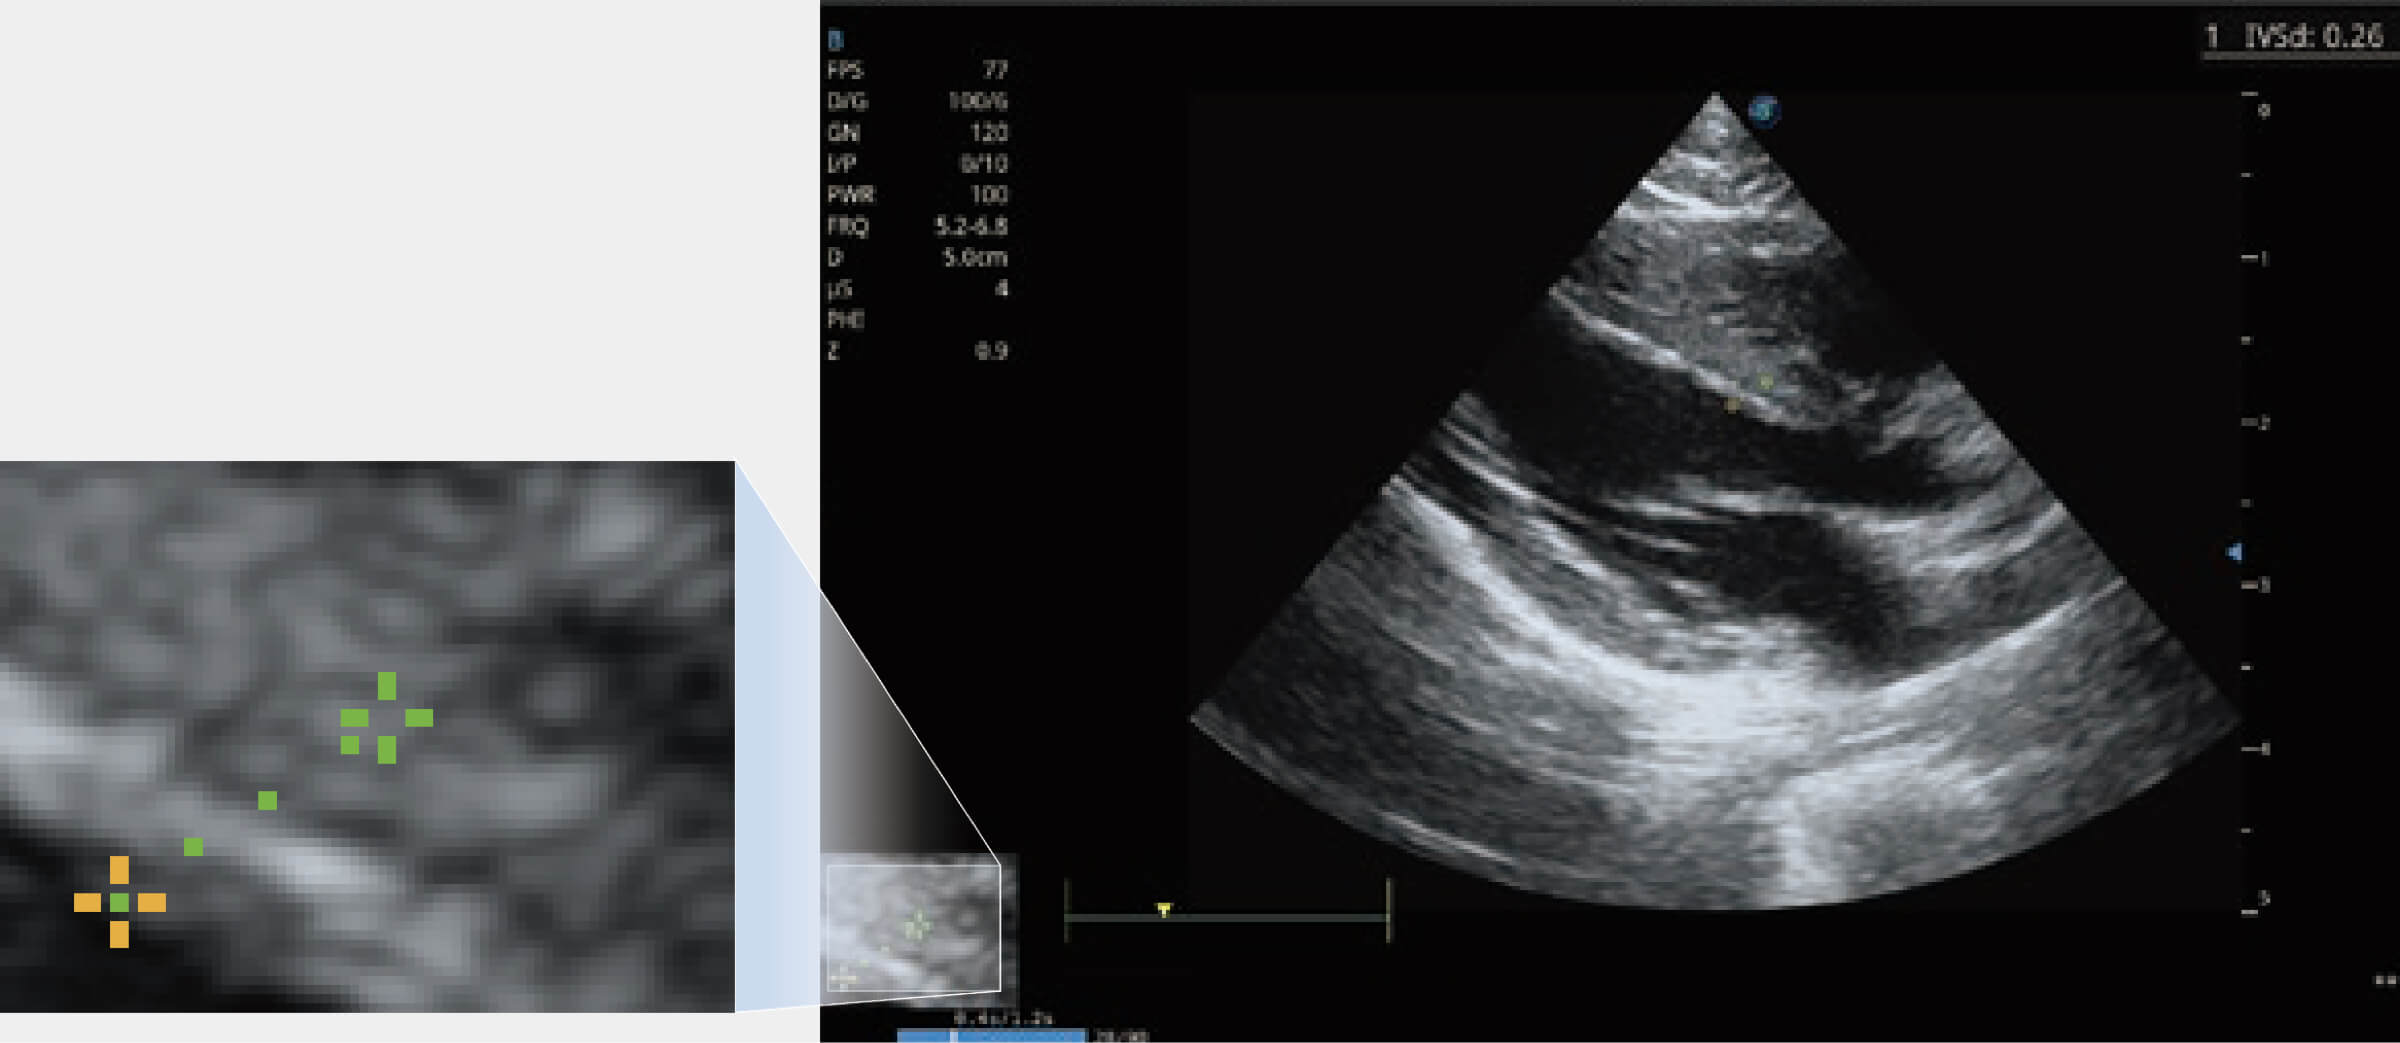

ProPet 80 配備了豐富的心臟探頭群、先進(jìn)的成像技術(shù)和專業(yè)的心臟測量工具,可幫助動物醫(yī)生為不同體型和生理結(jié)構(gòu)的動物提供心臟和心肌功能的全面評估。

通過360度任意調(diào)節(jié)3條M型取樣線,在同一心動周期上觀察心臟不同位置的運(yùn)動曲線,得到準(zhǔn)確的心功能測量數(shù)據(jù),有效評估心肌運(yùn)動及左心室功能。